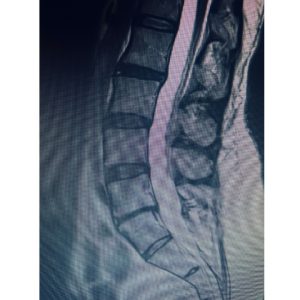

“This 53-year-old patient had a collapsed L5-S1 disc, retrolisthesis and foraminal stenosis contributing to severe low back pain. She had tried years of conservative (non-operative) treatment including physical therapy and injections without relief. At Texas NeuroSpine Surgery, we will always continue make every effort to treat your low back pain from a collapsed disc without surgery. However, surgery is appropriate for some carefully selected cases.

For this patient who had years of debilitating back pain, the solution was an ‘anterior-posterior’ or ‘front-back’ lumbar spine surgery (3rd photo). The surgery is also known as an ALIF (Anterior Lumbar Interbody Fusion) with posterior stabilization.